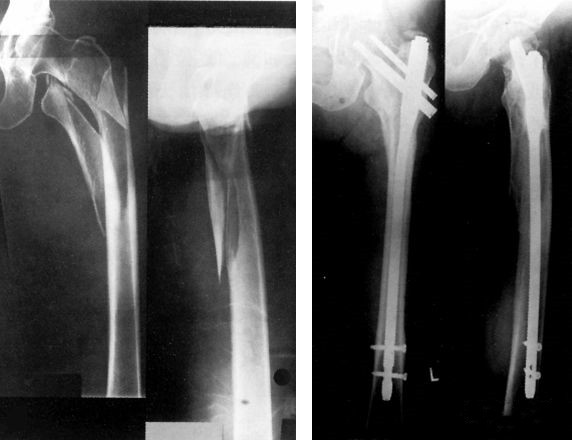

Une fois l'état général du patient sous contrôle, une ostéosynthèse, DHS, DCS et PFN, doit être réalisée.

Une fracture du col fémoral, en particulier une fracture intracapsulaire, peut mettre en danger l'approvisionnement en sang de la tête fémorale, il est donc nécessaire d'ouvrir la réduction et la fixation interne dès que possible.

Fixation interne : < 65 ans

Arthroplastie : > 65 ans

Si la chirurgie d'urgence n'est pas possible, une ponction articulaire et une aspiration d'hématome intra-articulaire peuvent être réalisées, et l'articulation de la hanche peut être maintenue en position de semi-flexion et de rotation externe.